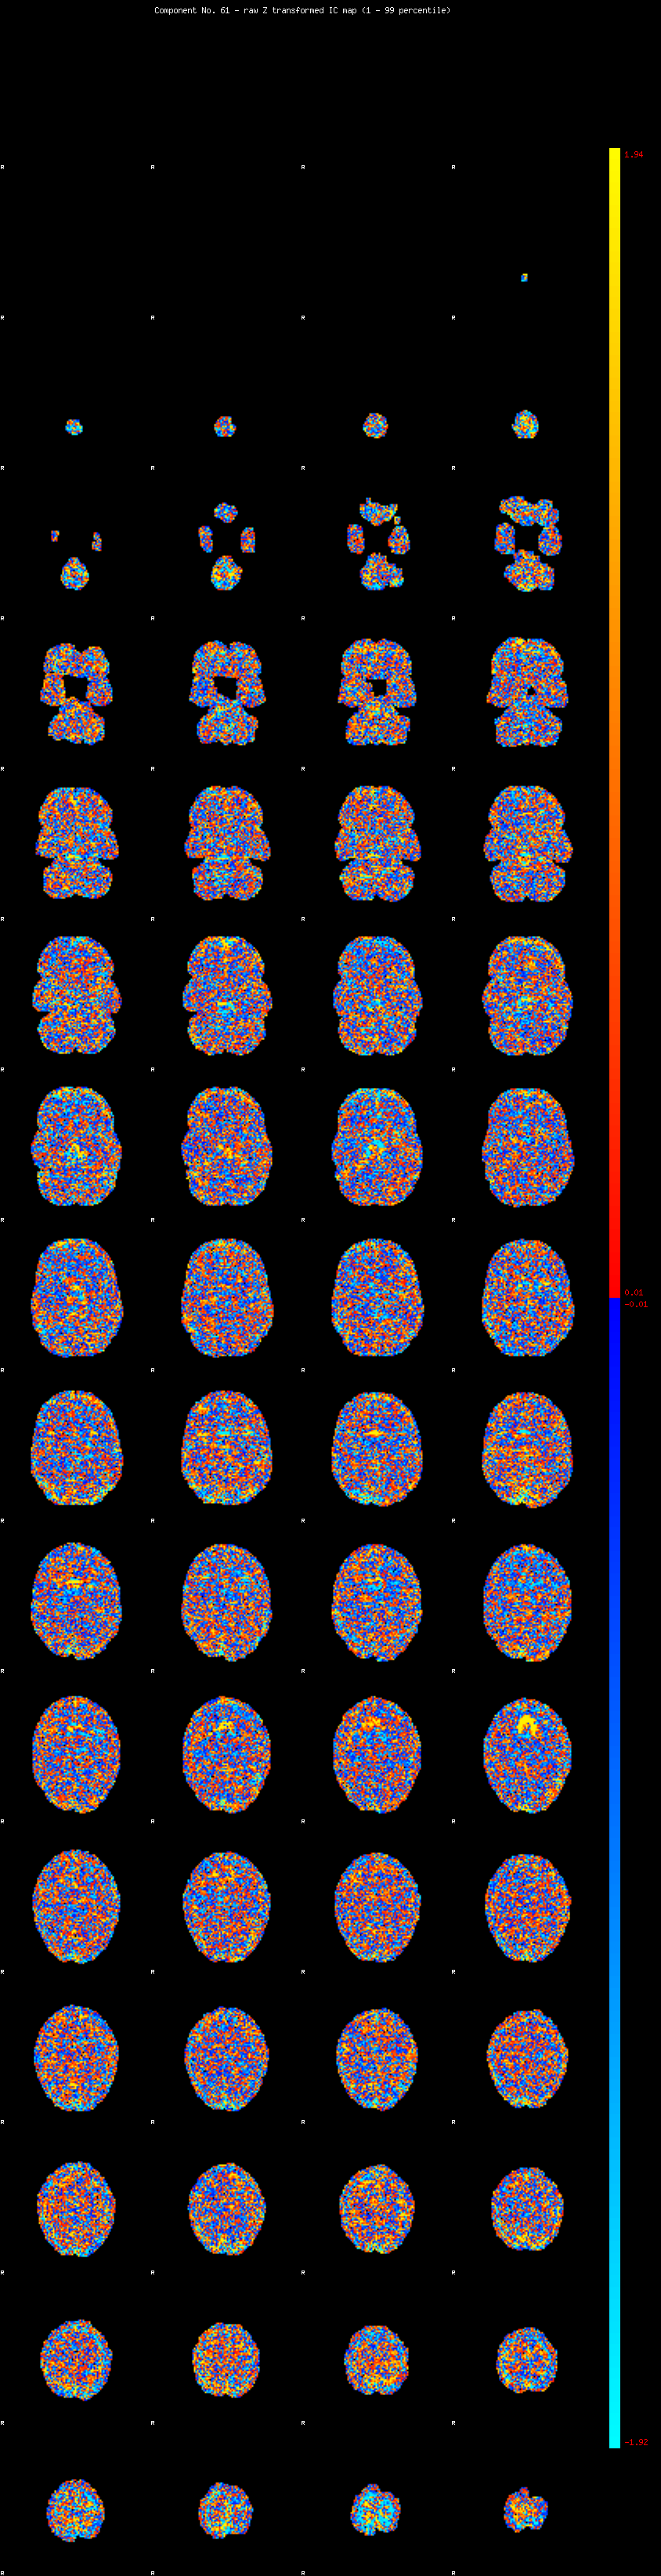

IC_61 Mixture Model fit

Means : 0.000000 2.263786 -2.155729

Vars : 1.000000 1.368815 1.073529

Prop. : 0.941875 0.028953 0.029172